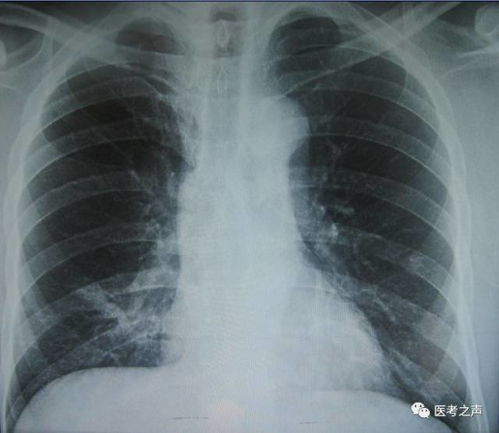

CT扫描具有定量分析能力,可以准确测量各组织的X射线吸收衰减值。这对于评估病变的大小、形态和性质具有重要意义。在X光检查中,由于缺乏定量分析能力,医生难以准确评估病变。

10. 定量分析:CT可以进行定量分析,如测量病变的大小、密度等,有助于评估病情和治疗效果。